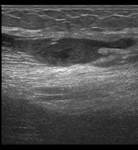

- Diagnóstico inicial: rotura fibrilar grado II en isquiotibiales (confirmada mediante ecografía).

Tras 8 semanas de tratamiento, el paciente logró una recuperación completa, reincorporándose a su actividad deportiva sin molestias ni limitaciones. La ecografía de control mostró una adecuada cicatrización de las fibras, y los test de fuerza confirmaron simetría con la pierna contralateral.